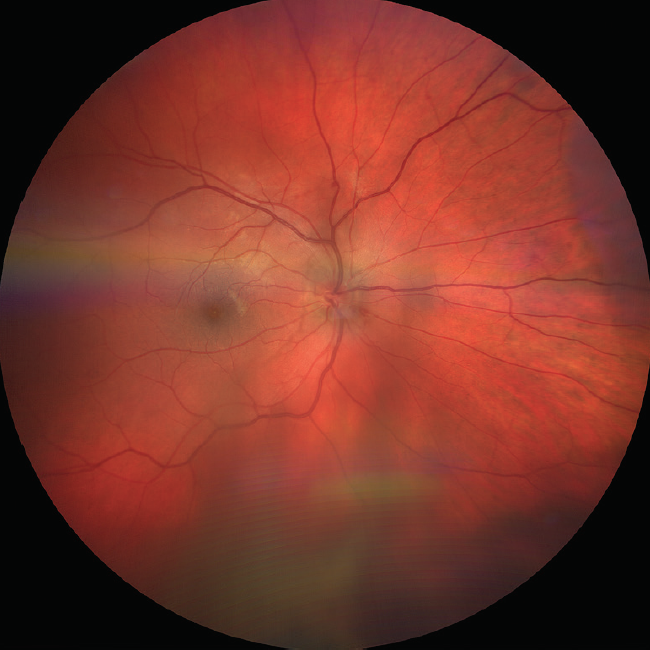

<p>Figure 2. Subhyaloidal hemorrhage and posterior vitreous detachment were observed on OCT.</p>

Figure 2. Subhyaloidal hemorrhage and posterior vitreous detachment were observed on OCT.

Interestingly, the fovea was spared by the subhyaloidal hemorrhage, allowing maintenance of good vision. This can be explained by the typical distribution of vitreomacular adhesion in people in this age group. The posterior vitreous is most adherent at the fovea, the optic disc, and around the arcades, whereas it is less adherent in the mid-macula. The relatively weaker adhesions provided a cleavage plane for the blood to spread in a donut shape, sparing the fovea. The distribution of the subhyaloidal hemorrhage, as well as a stage 1 posterior vitreous detachment,2 were confirmed on OCT (Figure 2).